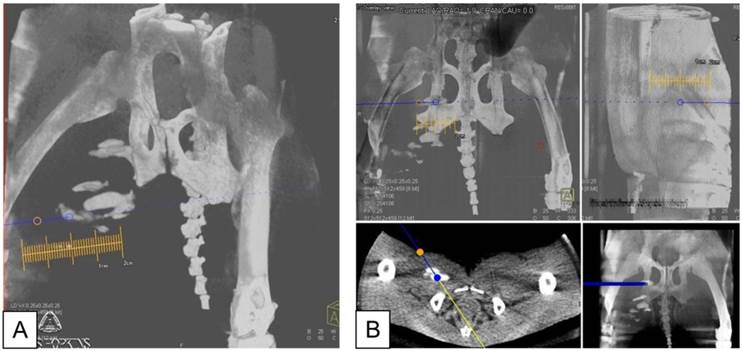

Figure 1

A: X-ray fluoroscopic overlay in oblique projection on the c-arm CT in preparation for needle targeting to PFOB and APA microcapsules injection sites. Orange circle indicates the skin entry point; blue circle shows the target point. B: Planning of the needle entry to the target point in coronal (top left), sagittal (top right), axial (bottom left), and multi-planar reformat (bottom right).